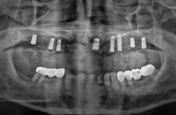

엄마 임플란트 해드려야해서 모시고 갔는데 왠만한 치과치료는 다 가능하네요~ 동네에 큰 치과병원이 있어서 든든해요 원래 치아가 약하셔서 이번에 효도할겸 임플란트 해드렸는데 자세하게 검사 해주시고 잇몸 위치, 뼈상태부터 어떤 치료를 왜 해야하는지 까지 설명을 해주셔서 좋았어요~ 아빠도 의사선생님 기술이 좋은거 같다며 ㅎㅎ 엄마 부러워 하셔서 예약 잡았어요